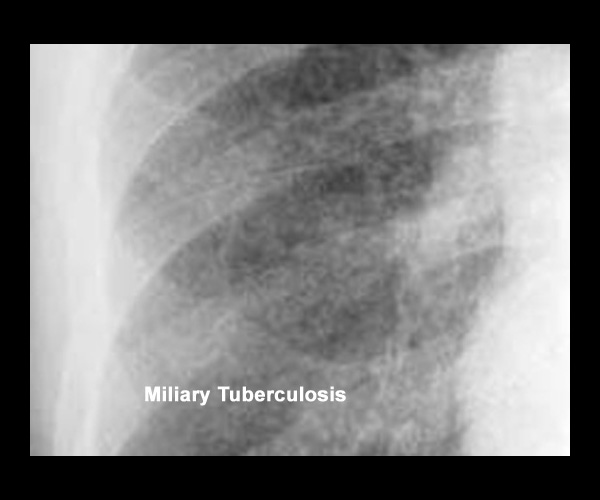

Miliary Tuberculosis

Bilateral diffuse <5mm nodules. Click on the image to see close up.